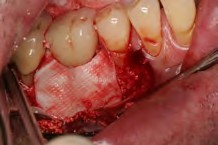

The entry of inflammatory cell infiltrate into the connective tissue (Figure 1 and Figure 2) differentiates peri-implantitis from peri-implant mucositis.1 Unlike a natural tooth—where periodontal fibers, transepithelial fibers, and gingival fibers absorb this exudate—none of these fibers are present around an implant (Figure 3). This allows the inflammatory cell exudate to directly enter the bone, resulting in bone loss and concomitant soft-tissue loss (Figure 4).1

Fig 1. In the pathogenesis of peri-implantitis, inflammatory cell infiltrate enters the connective tissue.

Figure 1